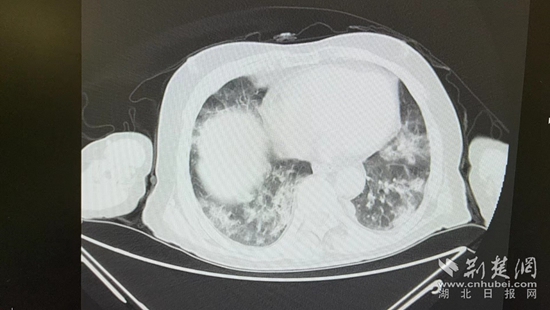

病情的突然恶化,会不会与近期的新冠病毒感染有关?虽然家属反映,曾多次在家自测抗原正常,但徐涛还是力排众议,说服老人进行核酸检测和肺部CT检查。结果显示核酸阳性,60%白肺,结合老人的表现,这正是一例典型的老年人“沉默性肺炎”。

胸部CT片。通讯员 供图